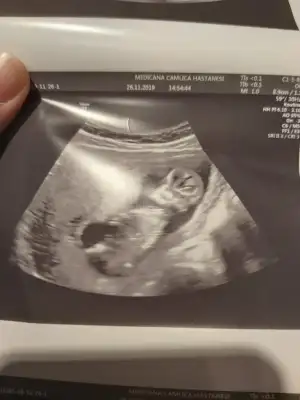

Benim de kız demiştinizKız bence

Teşekkürler doktor da kıza benziyor dedi ama bakalımKız bence

Öğrendiniz mi neymiş ben genelde kıza benzetiyorum nedenseBenim de kız demiştiniz![]()